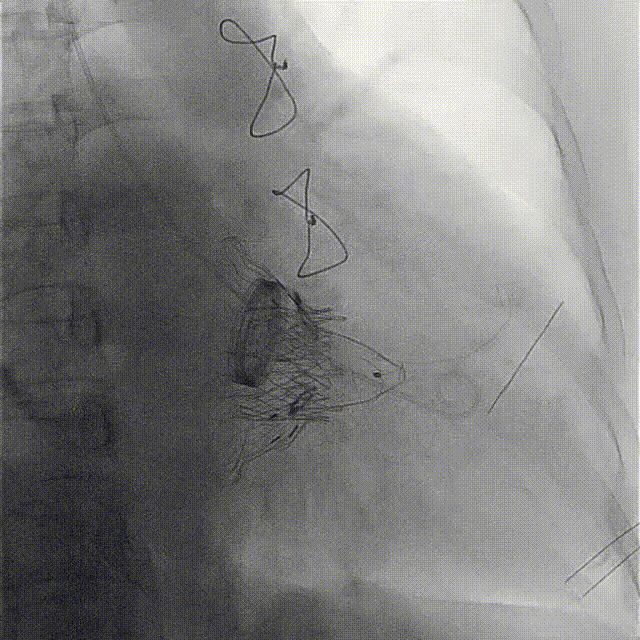

術前DSA

手術在全麻狀態(tài)下開展,海軍軍醫(yī)大學附屬長海醫(yī)院陸方林教授與廈門心血管病醫(yī)院王焱院長共同上臺,為患者進行手術。此次手術采用經右側頸靜脈入路的方式將輸送器送入患者心臟內,在TEE及DSA引導下調整輸送器頭端角度,使得輸送器與三尖瓣瓣環(huán)平面垂直。在輸送器進入右心室后釋放室間隔錨定裝置,而后釋放瓣葉夾持件(2個耳片結構)成垂直狀態(tài)。在TEE及DSA確定夾持件固定至三尖瓣葉根部且位于右室側后釋放人工瓣心房側盤片。隨后調整瓣膜同軸性以及室間隔錨定件位置(貼合室間隔),前推藏針管并固定,進而釋放室間隔錨定裝置,并再次確認瓣膜位置、穩(wěn)定性及同軸性,合攏輸送鞘后撤出輸送器,完成LuX-Valve Plus人工三尖瓣瓣膜的植入。

術后DSA